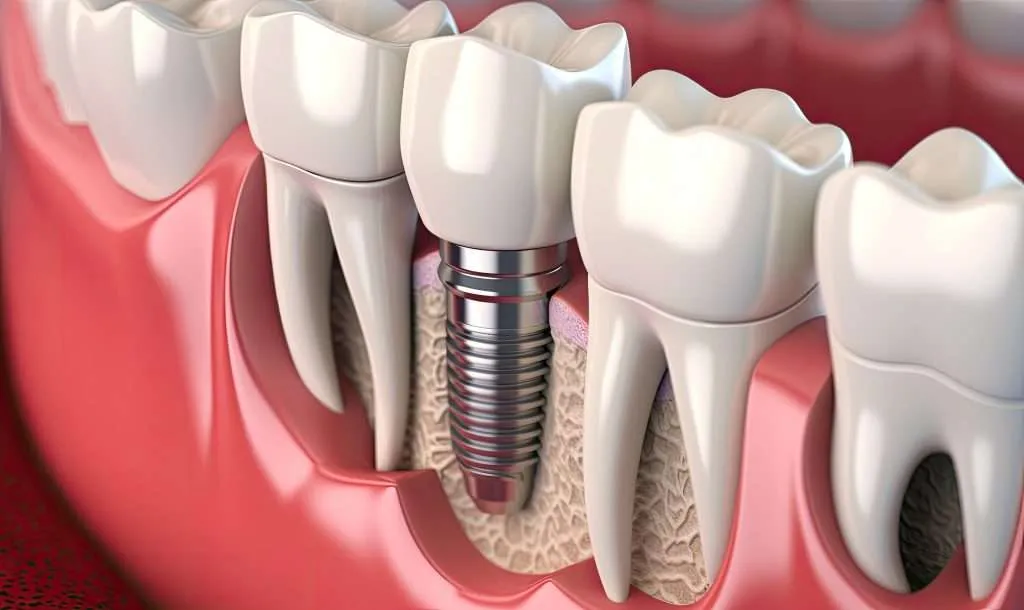

Un impianto dentale è una piccola vite, generalmente in titanio biocompatibile, che viene inserita nell’osso e svolge la funzione di radice artificiale su cui verrà poi fissato il dente sostitutivo.

L’intervento di inserimento dell’impianto avviene in anestesia locale e, nella maggior parte dei casi, non è doloroso. L’impianto viene posizionato all’interno dell’osso e successivamente coperto dalla gengiva per permettere il processo di osteointegrazione, cioè l’unione stabile tra osso e impianto.

L’osteointegrazione richiede generalmente da 2 a 6 mesi, a seconda della zona trattata e delle condizioni individuali del paziente. Durante questo periodo l’impianto si stabilizza e diventa una base solida per il dente definitivo.